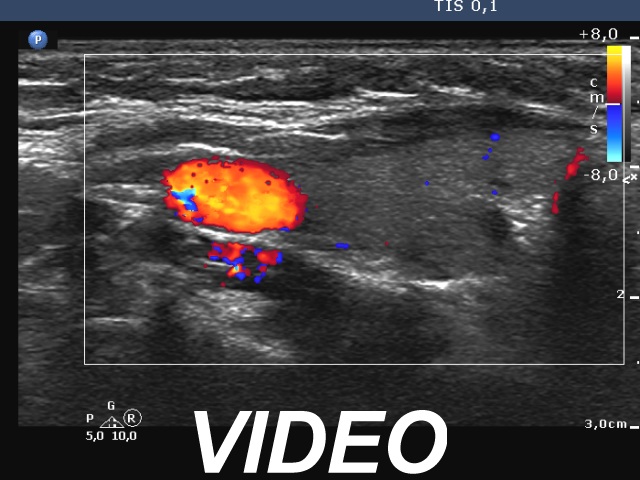

Ultrasonography. The thyroid was echonormal and had some minimally hypoechoic areas. A thick connective tissue band crossed the right lobe. Dorsal to this fragment the thyroid was very hypoechoic. On transverse scan, this area seemed to be a nodule. However, analysis of multiple sections revealed that this area was not a true nodule.

The echogenicity of a specific tissue is deeply influenced by ventral structures. The well-known examples are the cystic fluid and the macrocalcification. The first can cause acoustic amplification, i.e. the dorsal structures become lighter, more echoic, while the macrocalcification has the opposite effect, the so-called acoustic shadowing makes the dorsal tissue very hypoechoic.

In this boy, the thick connective tissue hindered the penetration of the ultrasound wave, therefore the dorsal structure became darker, hypoechoic. -